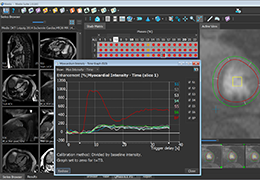

View X-Ray CT & MRI Scans Fast and Easily

Designed for surgeons, Pro Surgical 3D makes it easy to view patient scans quickly. Pro Surgical 3D facilitates the optimal 3D treatment and assessment workflows based on X-ray CT and MRI scans – and best of all, it’s FREE!

Traditional multi-planar slicing

Multi-planar slicing.

Side-by-side comparative assessment for pre- and post-operative scans.